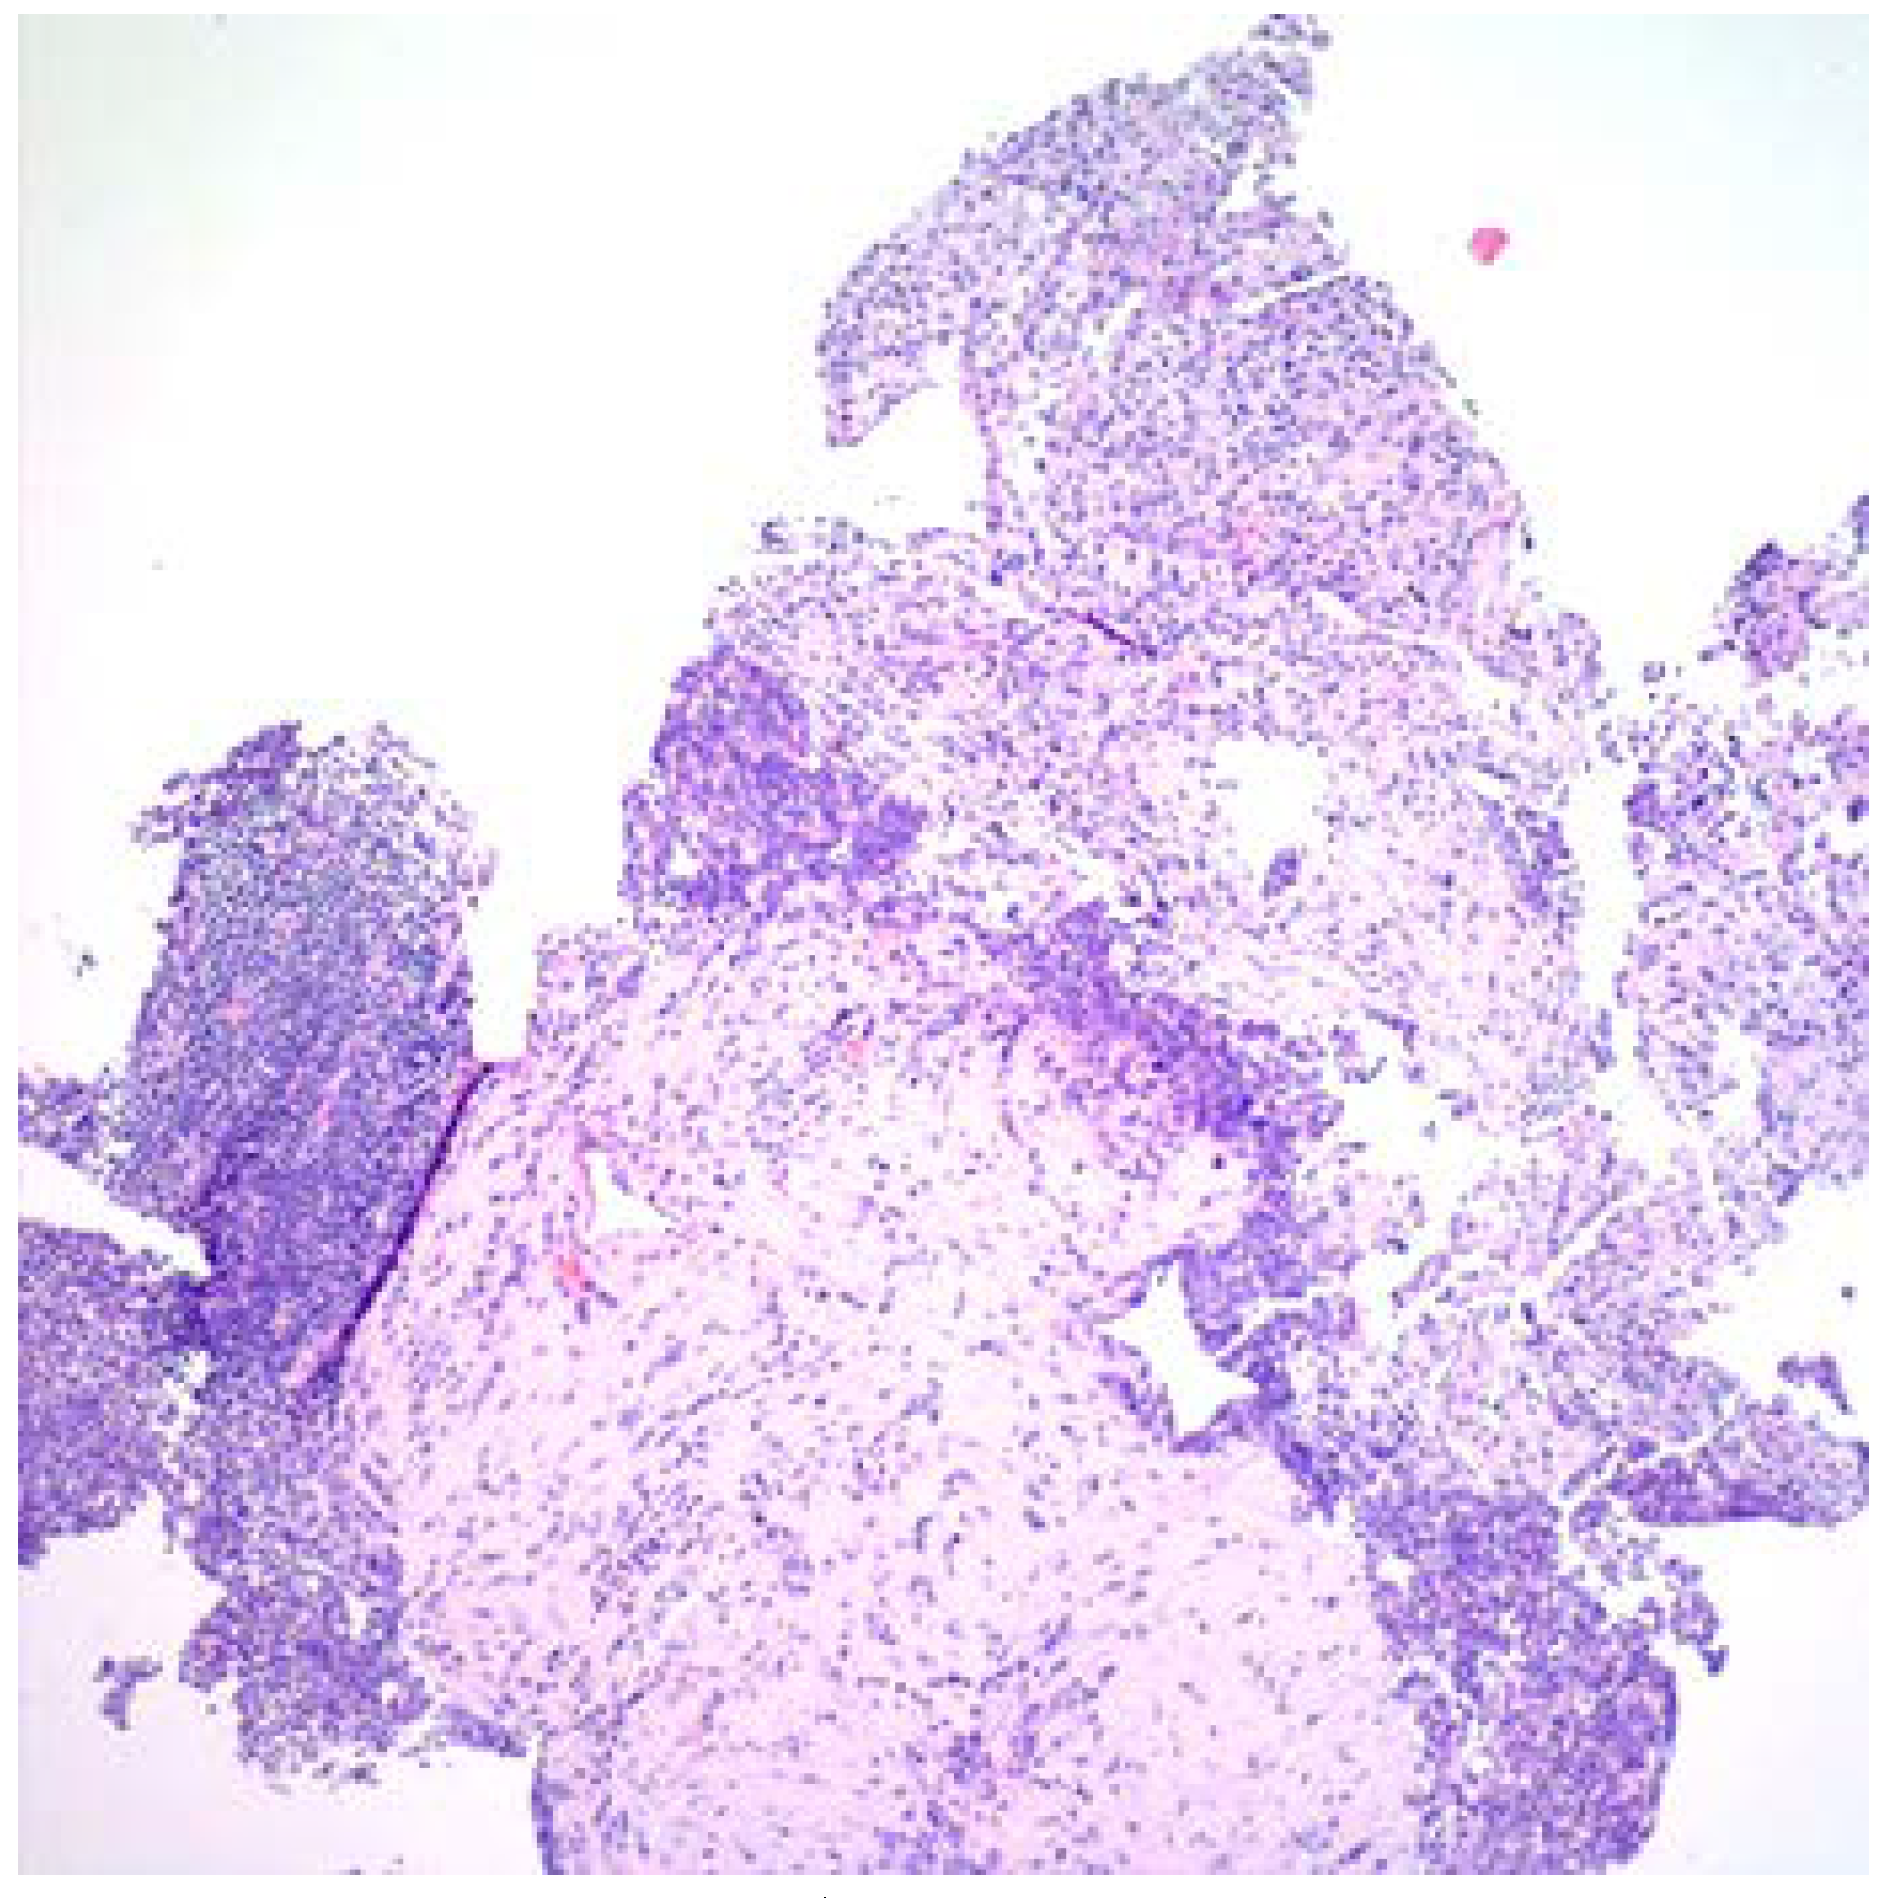

Fusobacterium nucleatum: A Cause of Subacute Liver Abscesses with Extensive Fibrosis Crossing the Diaphragm, Mimicking Actinomycosis

Case report